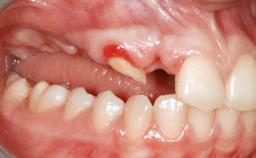

A 20-year-old woman was referred for implant therapy in 2004. Her medical history revealed no significant findings, and neither did she smoke nor take any medications. An extraoral examination revealed no abnormalities of the skin, hair or nails. The intraoral examination revealed only 11 permanent teeth clinically. These were normal in shape, size, and color. In addition, eight retained deciduous teeth (53, 62, 63, 71, 72, 73, 81, 82) were present. No abnormalities were detected during the general examination. The family history revealed that the patient’s father and two sisters were on record with similar conditions. The clinical examination revealed a thick gingival biotype. No recession of the attached gingiva was noted, but the retained deciduous teeth were mobile and unsightly. As a syndrome had not been diagnosed, the case was categorized as non-syndromic oligodontia.

Bone Augmentation Horizontal|Staged

Augmentation Materials Autogenous chips|Autogenous block(s)|Membrane

Soft Tissue Anatomy Intact Defective

Bone Volume Horizontally and vertically sufficient Horizontally deficient Deficient vertically or deficient vertically AND horizontally